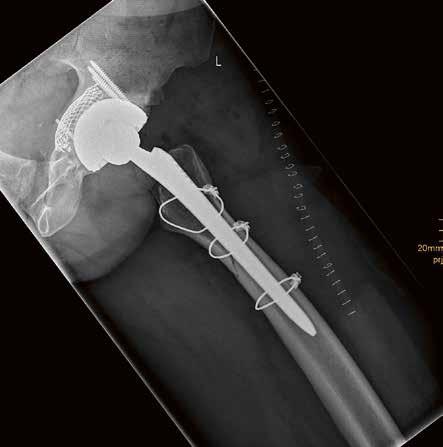

59-jähriger männlicher Patient mit Z.n. periprothetischer Fraktur nach Hüft-TEP; Abb. links: Oberschenkelaufnahme in Stitching-Technik zur präoperativen Planung, Abb. rechts: Post-OP-Dokumentation.